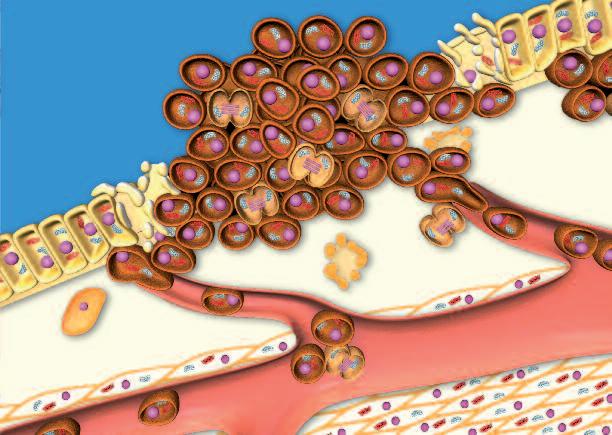

Le collagenasi, gli enzimi che digeriscono il collagene, sono prodotte da tutte le forme di cancro, indipendentemente dalla loro origine. L’illustrazione delle pagine a fianco mostra un esempio di questo processo: lo sviluppo del cancro al fegato.

Il fegato è l’organo centrale del metabolismo del corpo e, tra gli altri, è responsabile della neutralizzazione e della eliminazione delle tossine dal corpo. Tossine quali pesticidi, conservanti e molte droghe sintetiche farmaceutiche, sono le cause più comuni del cancro al fegato. Le cellule del fegato esposte a queste sostanze tossiche possono essere danneggiate o distrutte in modo permanente. La forma più frequente di danni porta ad una falsa ‘programmazione’ del materiale genetico della cellula (DNA).

Tale alterazione maligna del software della cellula segna l’inizio del processo tumorale attivando una serie di azioni biologiche che alla fine porta al cancro vero e proprio. Alcune di queste azioni sono essenziali per la crescita e la diffusione del cancro:

1. Moltiplicazione incontrollata delle cellule. Il software di una cellula tumorale è alterato in modo tale da rendere ‘immortale’ questa cella e farla moltiplicare all’infinito.

2 La produzione di massa di enzimi che dissolvono il collagene Il secondo presupposto del cancro è la produzione di enzimi che distruggono il tessuto connettivo circostante che, altrimenti, manterrebbe il tumore confinato.

Più enzimi che digeri scon o col lagene p rodu ce una cellula tumoral e, più aggressivo è il cancro e più velocemen te si diffon de attraverso il corp o, e più breve di venta l'asp ettativa di vita del paziente, semp re se tale meccan ismo non viene arrestat o.

Tumore al fegato

Cellule epatiche:

• Cellule sane (marroni)

• Cellule tumorali (verdi)

Le cellule tumorali presentano il software del nucleo alterato, questa modifica non prevede l’apoptosi (la morte fisiologica della cellula in caso di malfunzionamento o invecchiamento)

Le cellule tumorali

• si moltiplicano e

• producono collagenasi. Entrambe le produzioni sono stimolate senza limiti

Il disegno mostra gli enzimi prodotti dalle cellule tumorali epatiche che si fanno strada per espandersi.

La produzione di enzimi che digeriscono il collagene è il denominatore comune di ogni specie di tumore per crescere ed espandersi – è indifferente in quale organo la malattia compare.